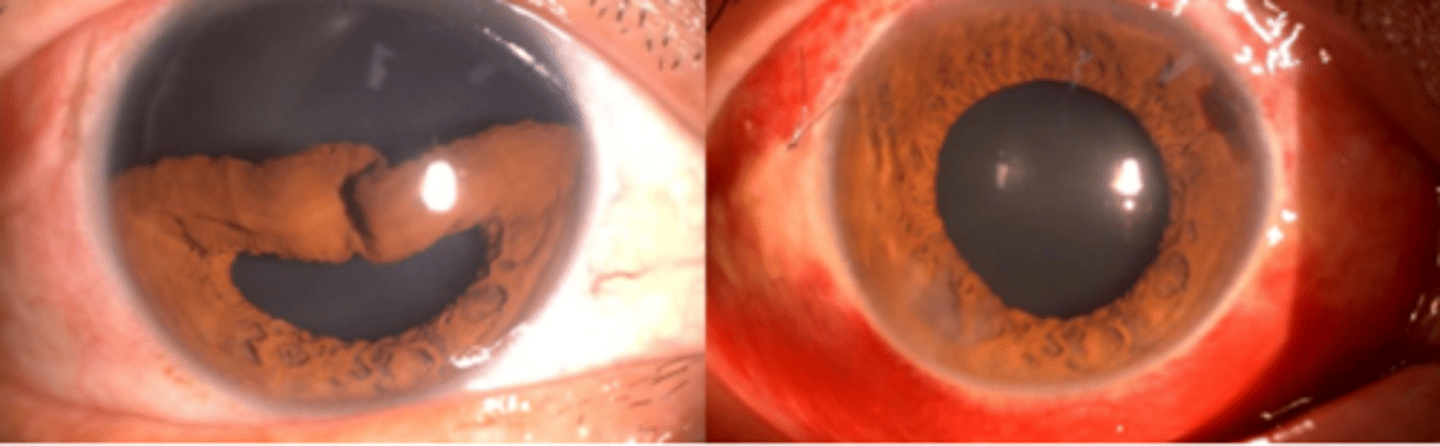

Iridodialysis

tear of the iris at the iris root. Blunt force trauma or penetrating injuries pose a risk. Can result in misshapen pupil, hyphema, damage to the angle, and traumatic iritis. Symptoms include glare, photophobia, diplopia, and cosmesis. Complications include lens dislocation, cataract, and secondary glaucoma.